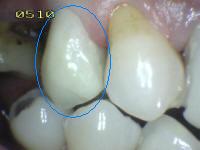

Obturación perdida

o fracturada |